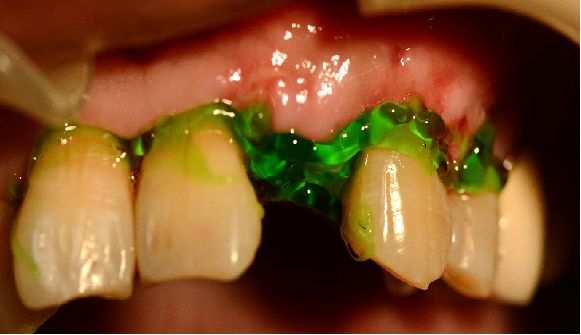

采用不切开骨膜的软组织扩张术——Soft Tissue Extend释放软组织张力

记录翻瓣后原始软组织瓣长度,使用软组织搔刮器(Soft Tissue Extender)冠根向搔刮软组织瓣。

在不切断骨膜的前提下,使用软组织刮治器反复搔刮软组织瓣,可以起到延长软组织瓣的作用。

使用软组织搔刮扩张前后对比:可见在不切断骨膜的前提下,使用软组织搔刮即可获得软组织瓣延长8-9mm。